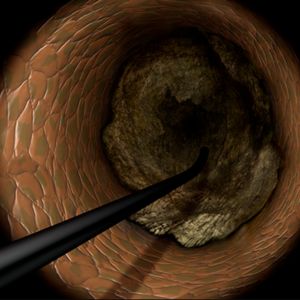

From the era of Plain Old Balloon Angioplasty (POBA) to bare-metal stents (BMS) and subsequently drug-eluting stents (DES), PCI has evolved to become the primary treatment modality for increasingly complex lesions. Among these, chronic total occlusions (CTOs) were considered the "last frontier" of PCI, prompting the development of techniques to guide wires through completely occluded lesions.

In the mid-to-late 2000s, the retrograde approach was introduced, leveraging collateral channels for wire crossing, significantly improving the success rates of CTO-PCI. This technique gained widespread attention due to the expertise of Japanese operators, elevating the global recognition of Japan's contributions. However, the use of delicate collateral channels posed challenges, particularly for less experienced interventional cardiologists, leading to complications such as perforations. Consequently, enthusiasm for CTO-PCI waned in Western countries, where its perceived lack of reproducibility kept it relegated to the realm of mastery-level procedures.

The 3D wiring technique was further refined by expert operators across Japan, eventually establishing Tip Detection Antegrade Dissection Re-entry (TD-ADR) as a new standard in CTO-PCI. TD-ADR reignited global interest in CTO-PCI by providing a more systematic and reproducible methodology. More recently, HydroDynamic Contrast Recanalization (HDR) has emerged as a technique for performing antegrade CTO-PCI, leveraging the synergistic use of contrast microinjections and polymer-jacketed wires to further expand the technical options available for CTO-PCI.